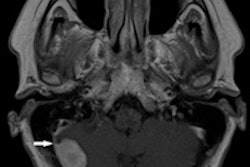

The smallest metastasis detected by whole-body MRI was 3 mm in the liver, while the largest metastasis missed was 5 mm in the brain, he said.

- Brain: 55%